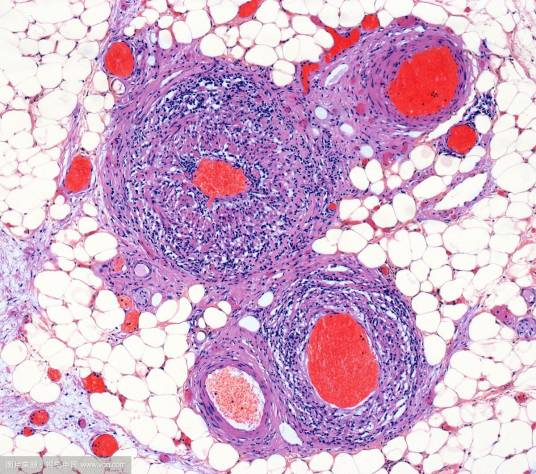

炎症细胞,参与炎症反应的细胞。白细胞渗出是炎症反应最重要的特征。在渗出液中,含有各种炎症细胞:淋巴细胞、浆细胞、粒细胞(嗜酸、嗜碱性、中性)和单核细胞等。炎症细胞也包含:“组织固有细胞”,例如巨噬细胞、肥大细胞和内皮细胞等。